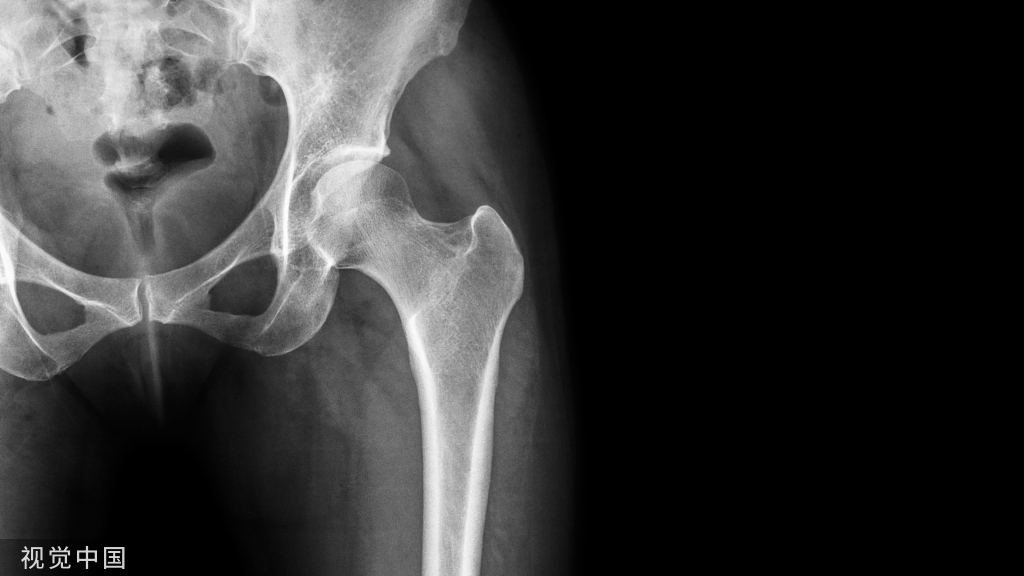

左上:股骨颈头下骨折

右上:股骨颈体部骨折

左下:股骨颈基底部骨折

右下:股骨粗隆间骨折